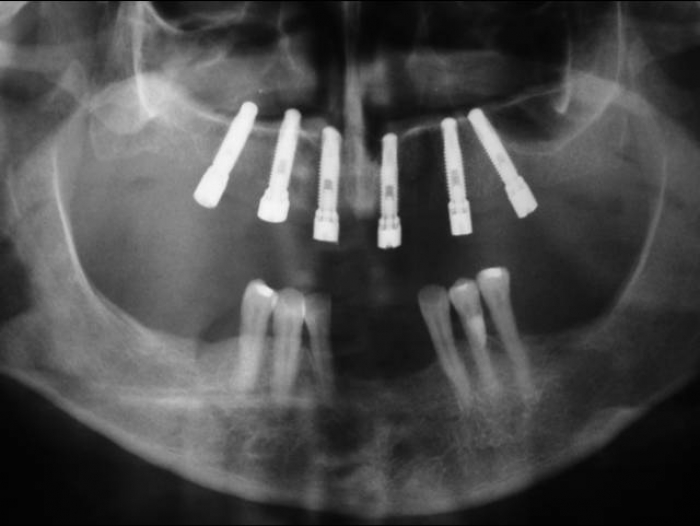

Raio X inicial